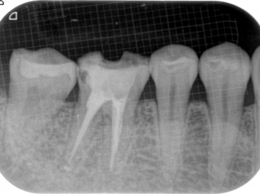

緊密な根管充塡

清潔な無菌的な根管の清掃が終了したら、緊密に根管充塡を行います。レントゲンで白く写る部分です。

根管治療の最後の処置です。根管の解剖学的な形態、彎曲度合い等によって数種類の根管充塡システムを当院では使い分けています。